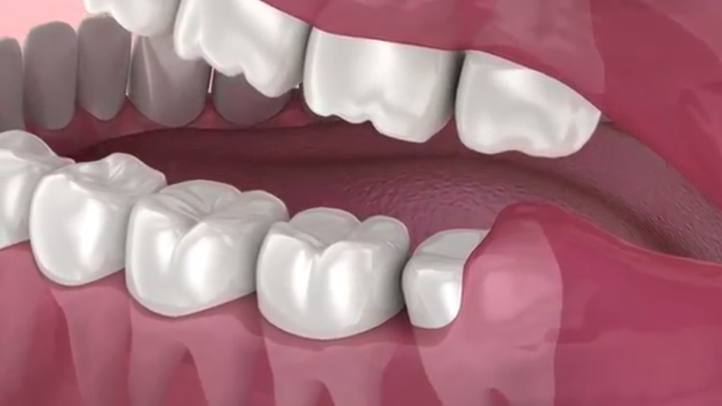

How Are Wisdom Teeth Removed?

Wisdom Teeth

The relative ease at which your dentist or oral surgeon can extract your wisdom teeth depends on their position and stage of development. Your oral health care provider will be able to give you an idea of what to expect during your pre-extraction exam. A wisdom tooth that is fully erupted through the gum can be extracted as easily as any other tooth. However, a wisdom tooth that is underneath the gums and embedded in the jawbone will require an incision into the gums and then removal of the portion of bone that lies over the tooth. Often, for a tooth in this situation, the tooth will be extracted in small sections rather than removed in one piece to minimize the amount of bone that needs to be removed to get the tooth out.